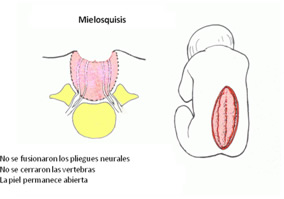

MIELOSQUISIS O RAQUISQUISIS

Es el tipo más grave de espina bífida ya que se produce antes de los 28 días de gestación.

En estos casos no hay quistes pero la médula espinal del área afectada está abierta permite el escurrimiento de LCR.

Tiene la apariencia de una llaga abierta en el medio de la espalda con placa neural en su centro.Es por esto que es más difícil de distinguirla en los ultrasonidos del embarazo.

Suele interpretarse erróneamente como mielomeningocele roto. La raquisquisis o mielosquisis, no siempre es mortal, pero deja siempre una grave secuela en la función medular y provoca importantes problemas clínicos.

- La exposición de la médula malformada y el escurrimiento externo de LCR, obligan a operar en las primeras horas de vida para evitar infecciones y así, debe tratarse como urgencia antes que se agregue meningitis.

- La hidrocefalia que aparece luego del cierre quirúrgico de la lesión es de buen pronóstico funcional.